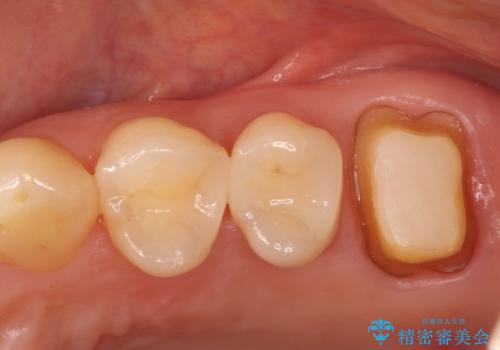

- 左上6番目の奥歯に違和感があるとの主訴でご来院されました。

レントゲンおよび精密診査の結果、過去に根の治療を終えた根尖部に再び炎症(根尖病変)が認められました。被せ物の適合が悪くなっていたことから、隙間から細菌が侵入したことが原因と考えられます。歯を長持ちさせるため、まずは古い被せ物と土台を外して根の内部を徹底的に洗浄する再根管治療を行い、その後、適合性と審美性に優れたオールセラミッククラウンで修復する計画を立案しました。